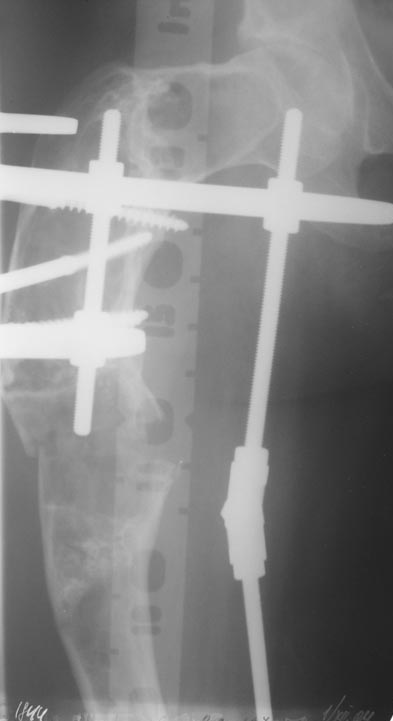

Уважаемые коллеги! Большое спасибо за живой отклик и предложения по тактике лечения. Больной произведен первый этап - стержневой аппарат издвух баз, кортикотомия, остеоклазия и начата коррекция в аппарате. Почти исправлен угол, не сегодня укорочение 2см. Когда завершим коррекция, представлю рентгенограммы.

В ноябре этого года я обращался с просьбой о помощи в выборе тактики лечения больной с деформацией бедра на почве фиброзной дисплазии. Были получены интересные и очень полезные советы по операции.

Хотелось бы показать, что получилось в результате.

Операция выполнялась с помощью А.Н.Челнокова. Очень понравилась технология выполнения блокируемого остеосинтеза с использованием спицевого дистрактора, модифицированный гвоздь с латерализованным проксимальным отделом и возможностью многовинтовой фиксации проксимального и дистального участков бедра.